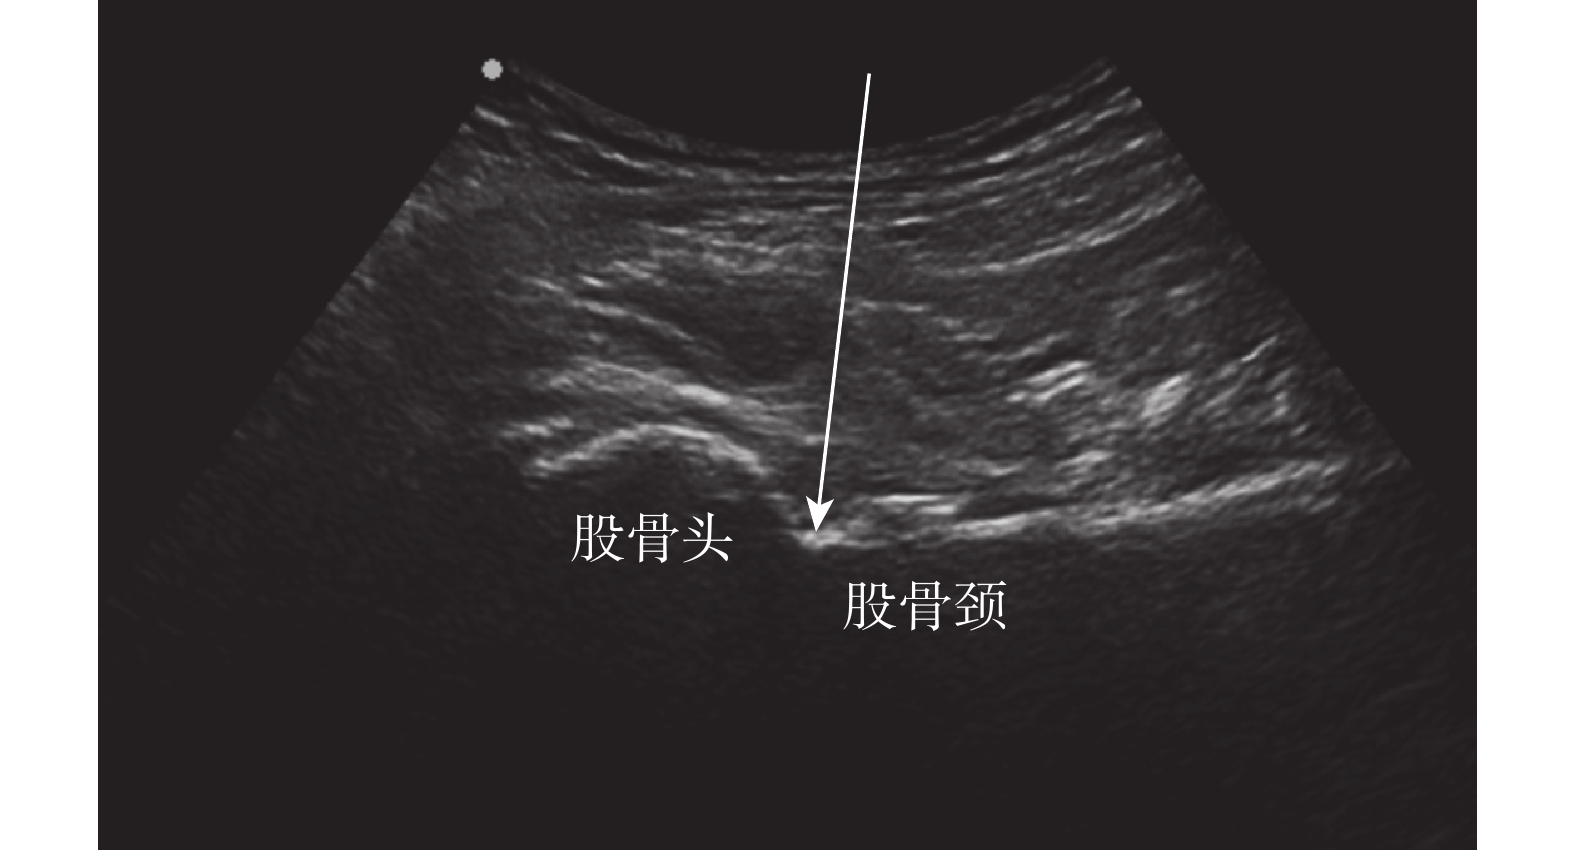

選擇彩色超聲系統(日本柯尼卡美能達公司,SONIMAGE HS1)和低頻凸陣探頭(C5-2,3~5 MHz)進行超聲引導注射,注射器連接一次性使用無菌注射針頭(浙江康德萊醫療器械股份有限公司,0.9×80 TWLB)備用。患者取仰臥位,患肢外展 10~20°,觸診腹股溝區標記股動脈體表位置;常規行消毒鋪巾,超聲探頭長軸與股骨頸平行,置于髖關節上方,顯示髖臼、股骨頭、股骨頸和髖關節腔;確定注射靶點,應用彩色多普勒觀察毗鄰血管情況,確定進針點和路徑;采用“平面外進針”方式,實時調整針尖方向至針尖進入髖關節腔,回抽無積液或血液后注入 PRP 4~5 mL,觀察 PRP 的彌散情況(圖 1)。拔針后按壓進針點 5~10 min,確定無明顯出血后再次消毒和覆蓋敷料,無痛范圍被動活動關節促進 PRP 彌散。告知患者相關注意事項,觀察 20 min 無不良反應后方可自行離開。所有股骨頭壞死患者治療方案均為每周注射 1 次,連續治療 4 周,注射完成后接受居家康復鍛煉指導,超聲引導注射治療和康復鍛煉均由同一名有多年超聲引導下注射經驗的康復科醫師完成。

白箭示進針方向及注射靶點